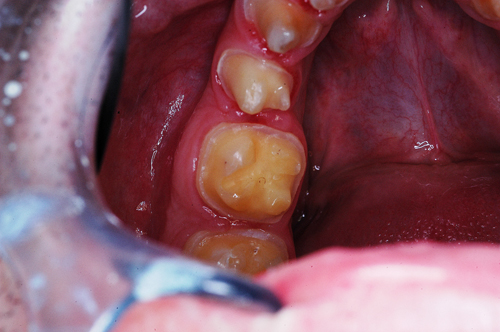

REHABILITACION ORAL MEDIANTE CORONAS DE PORCELANA DE ALTA DENSIDAD Protocolo D.A.T.O. CASO CLINICO: Paciente 24 años, bruxómano, atresia maxilar, referido por ortodoncista para realizar rehabilitación oclusal . Se observa a la inspección la presencia de una hipoplasia adamantina en todos los dientes anteriores, carencia de Guía Anterior , evidentes signos de Facetas Parafuncionales de Desgaste en los posteriores, y una marcada convergencia de los ejes dentarios ápico oclusal, tanto en el maxilar superior como en el inferior, siendo el superior el mas difícil de resolver dado que la inclinación de la Curva de Wilson es inversa a lo que presenta el enfermo. Radiograficamente sin patologías presentes. No presenta movilidades dentarias ni síntomas articulares en las ATM. Debido a la excesiva contractura de su musculatura, se realiza la relajación obviando el uso corriente de las Laminillas de Long, reemplazando el método por un Jig de Lucia el que se deja en boca desde la noche anterior a la cita, advirtiendo al paciente que no debe quitarlo en ningún momento , ya que de hacerlo se repetirían los engramas musculares anómalos que el enfermo presenta. En esas condiciones se toman registros intermaxilares mediante silicona de registros, y se registra el maxilar superior respecto del plano de Frankfort mediante arco facial estático. Se llevan a cabo los encerados correspondientes y se construye en base a ellos el primer juego de provisionales, los que no son cementados debido al perfecto anclaje que presenta. Transcurridos seis meses del uso de provisionales , durante los cuales se ha observado la Oclusión en Relación Céntrica (ORC) inalterable, la ausencia de desgastes patológicos (en las provisorias) y la ausencia de síntomas articulares y musculares, deducimos que el paciente se mantiene en una orto función adecuada, por lo cual comenzamos su rehabilitación definitiva construyendo su Guía Anterior ( determinante primario de la oclusión) en porcelana sobre porcelana de alta densidad.. Observamos los espacios correspondientes en los sectores posteriores y las Disclusiones de los mismos. Los tallados ha sido realizados mediante el concepto de Tallados Gnatológicos, recreados por el Prof. Alvarez Cantoni bajo la denominación de “Preparaciones Racionales”( PREPARACIONES RACIONALES EN PRÓTESIS PARCIAL FIJA. Ed. Hacheace) probando finalmente el trabajo luego de varios días de cementado provisional, y observando la adaptación periférica del borde cavo superficial , su aspecto estético y el importante factor disclusivo : CURVA DE WILSON. y verificando la eficacia lograda mediante una Oclusión Mutuamente Compartida, en la observación de una Disclusión derecha en el Lado de Trabajo y no Trabajo de una disclusión izquierda como así también en la disclusión propulsiva Utilizamos papel de articular de ocho(8) micras para verificar la eficacia de las disclusiones. y de los puntos interoclusales de contacto ANTES DESPUES

Luego de un par de entrevistas, se le informa acerca de la hipofunción masticatoria evidente, producto de la destrucción no solo de las piezas anteriores, sino también de la paulatina generación de Facetas Parafuncionales de Desgaste que determinan una eficacia masticatoria deficiente.

Facetas estas donde puede observarse el típico fenómeno de “DESGASTE EN OLLA”, constituido por el facetamiento doblemente profundo de las Cúspides Estampadoras respecto de las Cúspides de Corte.